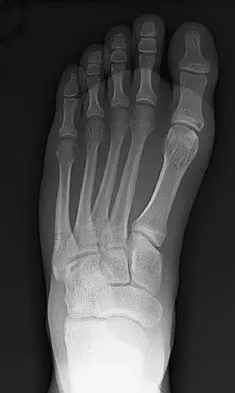

An active 47-year-old woman with rheumatoid arthritis reports forefoot pain and deformity and has difficulty with shoe wear. Examination reveals hallux valgus and claw toes. A radiograph is shown in Figure 10. What is the most appropriate surgical treatment?

Explanation

Rheumatoid arthritis commonly affects the metatarsophalangeal joints, which become destabilized with time resulting in hallux valgus and dislocated lesser claw toes. The result is metatarsalgia as the dislocated claw toes "pull" the fat pad distally. Severe hallux valgus reduces first ray load, which compounds the metatarsalgia because the load is transferred to the lesser metatarsal heads. First metatarsophalangeal arthrodesis restores weight bearing medially and corrects the painful bunion. Metatarsal head resection slackens the toe tendons to allow correction of the claw toes by whatever means necessary and decreases plantar load over the forefoot. Rheumatoid arthritis in the first metatarsophalangeal joint will continue to progress if osteotomies or a Lapidus procedure are performed. Keller resection arthroplasty increases transfer metatarsalgia and reduces push-off power during gait. Flexor-to-extensor tendon transfer of the lesser toes does not address the metatarsalgia and does not correct the dislocation of the metatarsophalangeal joint. Coughlin MJ: Arthritides, in Coughlin MJ, Mann RA (eds): Surgery of the Foot and Ankle, ed 7. St Louis, MO, Mosby, 1999, p 572.